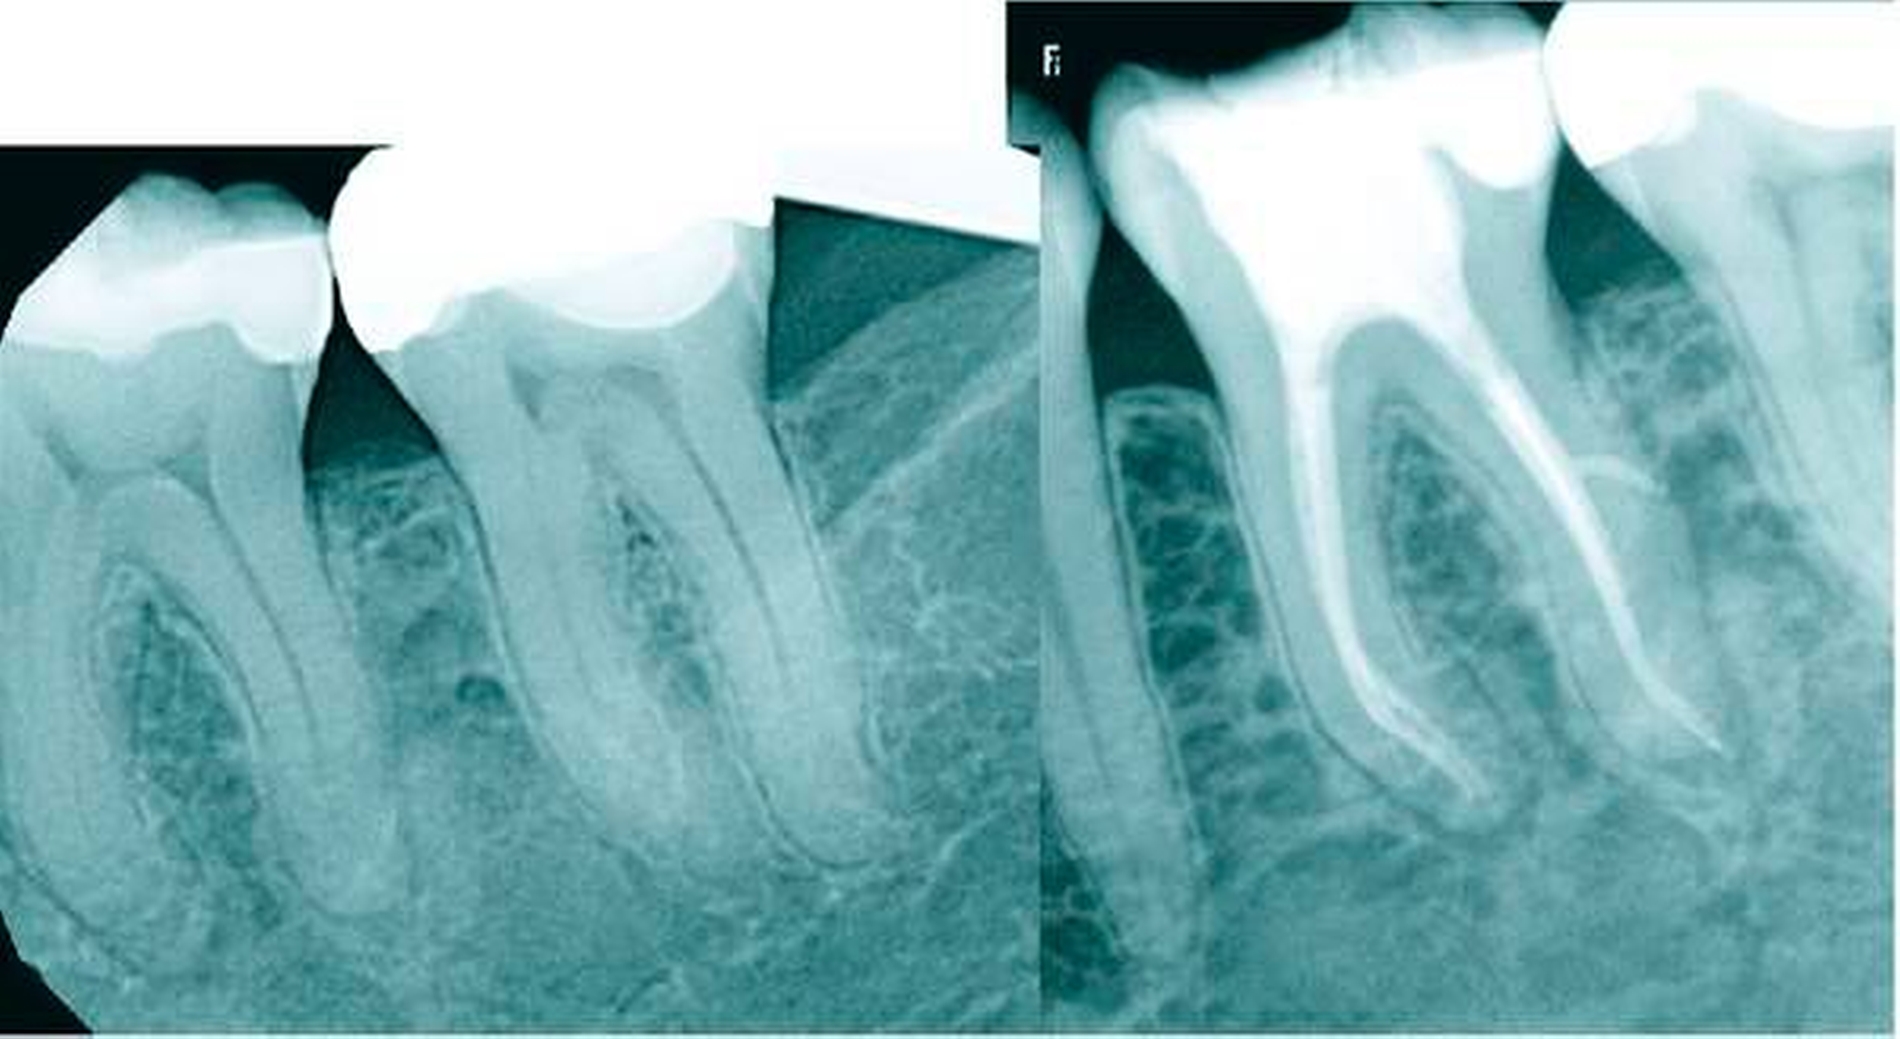

In der kaukasischen Bevölkerung haben Unterkiefer-Molaren in den meisten Fällen zwei Wurzeln. Nur in seltenen Fällen wurden zusätzliche Wurzeln, beispielsweise eine zusätzliche distolinguale Wurzel (Radix entomolaris, Abbildung 4) in den mandibulären ersten Molaren beschrieben [De Moor et al., 2004]. Schon im Jahr 1844 wurde eine solche zusätzliche distolinguale Wurzel von Carabelli erwähnt [Carabelli, 1844]. Abella et al. [Abella et al., 2012] gaben die Häufigkeit zusätzlicher distolingualer Wurzeln in den ersten mandibulären Unterkiefer-Molaren mit 14,4 Prozent an. Das Vorhandensein dieser Wurzeln korrelierte mit bestimmten ethnischen Bevölkerungsgruppen. So wurde die zusätzliche Wurzel deutlich häufiger in Populationen mit mongolischer Herkunft gefunden, beispielsweise bei Chinesen, Inuits und amerikanischen Ureinwohnern [Abella et al., 2012]. Cantatore et al. gaben das Vorkommen von Radix entomolaris in einer mongolischen Bevölkerungsgruppe mit einer Häufigkeit zwischen 5 Prozent und mehr als 30 Prozent an [Cantatore et al., 2009]. In einer Studie von Gu et al. [Gu et al., 2010] wurde in einer chinesischen Population ein Vorkommen von 32 Prozent ermittelt. Bisher wurden keine geschlechtsspezifischen Unterschiede in der Prävalenz einer zusätzlichen Wurzel erkannt. Die distolinguale Wurzel wird entweder als getrennt oder als teilweise in die andere Wurzel integriert beschrieben.

Wenn eine Radix entomolaris vorhanden ist, muss man häufig mit einer eher schwierigen mechanischen Aufbereitung rechnen. Üblicherweise ist die Wurzel kleiner als die distobukkale Wurzel. Im Allgemeinen hat sie einen größeren Krümmungswinkel, ist aber abrupter gekrümmt und hat somit einen kleineren Krümmungsradius als die distobukkale Wurzel (Abbildungen 4b und 4c). In der Mehrheit weisen die dreiwurzeligen Unterkiefer-Molaren vier getrennte Wurzelkanäle auf, wobei in der mesialen und in der distobukkalen Wurzel häufig akzessorische Kanäle vorhanden sind [Gu et al., 2011]. Mithilfe von mesioexzentrischen periapikalen Röntgenaufnahmen (25 °) oder einem DVT kann eine Radix entomolaris röntgenologisch diagnostiziert werden [Abella et al., 2012]. Die herkömmliche, dreieckige Zugangskavität sollte in diesem Fall zu einer Trapezform modifiziert werden, um einen geraden Zugang zu der meist gekrümmten Wurzel zu ermöglichen [De Moor et al., 2004]. Der durchschnittliche Abstand zwischen der distolingualen und der distobukkalen Kanalöffnung wurde in einer Studie mit 2,93 mm angegeben [Gu et al., 2010]. Während der mesiobukkale, der mesiolinguale und der distobukkale Kanal eine eher ovale Kanalform aufweisen, ist der distolinguale Kanalquerschnitt relativ klein und rund.